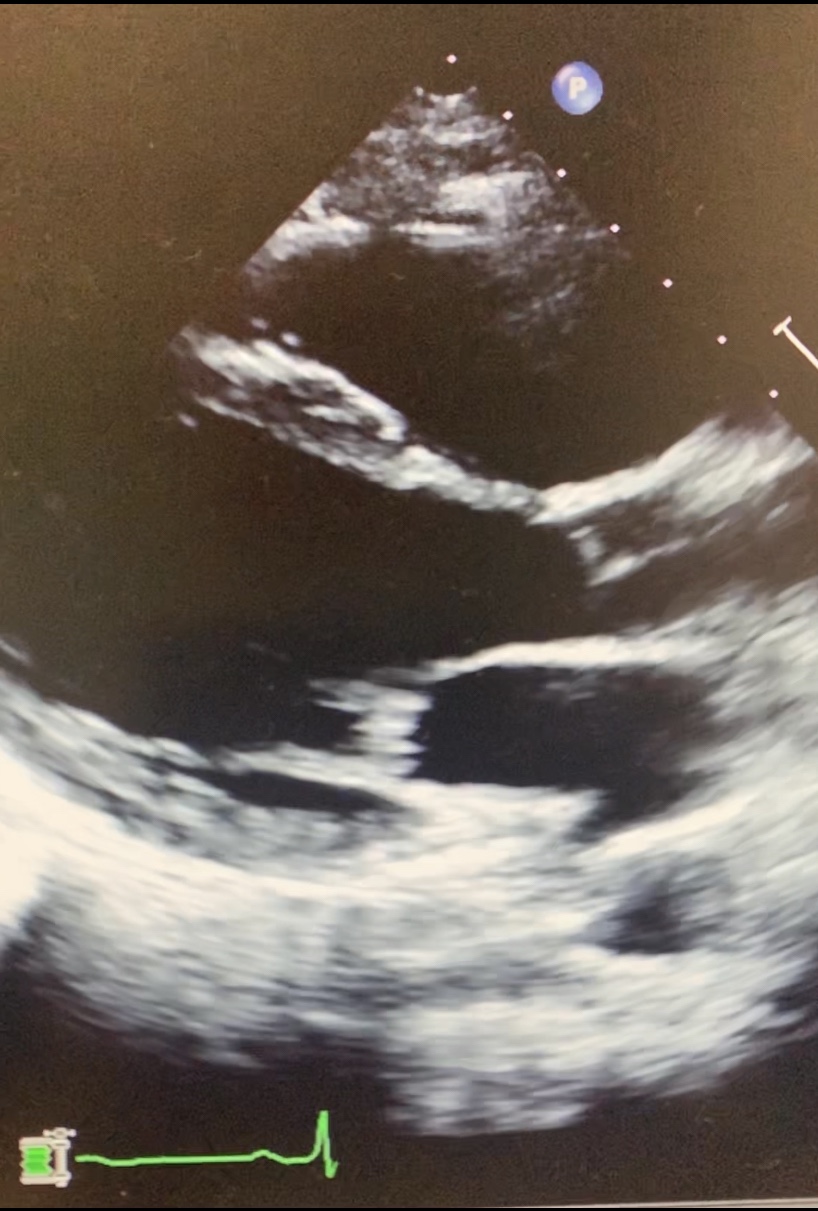

- Diagnostics: 2D echo, CFD, CWD/PEDOF.

VALVULAR STENOSIS

- Is the narrowing, thickening, fusion, or blockage of valve that obstructs blood flow through the valve; 3 levels: proximal (before valve), at the level of the stenosis (at the valve) and distal (after the valve).

- At the level: DOMING – when leaflets “round inwards” and don’t close fully. Increased pressure pushes on the undersurface of the tethered leaflets to cause doming. Thickening/fusion/calcification of the valve leaflets decreases the valve area within its orifice.

- Distal to the stenotic valve: turbulent flow, pressure decreases. (CFD more often). Mosaic pattern Doppler – red blood cells are traveling in multiple directions. Severe stenosis -> smaller area, greater velocity, more turbulent flow. REMEMBER: the atrium or ventricle has to squeeze harder to get the blood out. Decreased flow distal to the stenosis decreases the distal pressure. PG generated by the stenosis <36mmHG mild, 36-64mmHG moderate, >64 mmHg Severe.